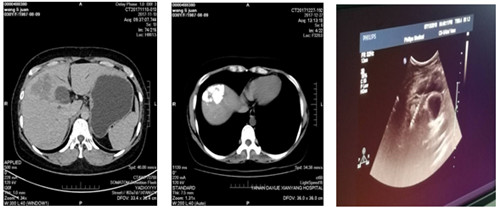

2018年5月前我院肿瘤胸外科收入一年轻女性患者,检查确诊为肝癌,经肿瘤多学科会诊后,行多次肝动脉灌注化疗栓塞术,治疗过程顺利,现复查CT示碘油沉积区域面积较前减小。为使病人得到最佳治疗,在我院肿瘤病院张海涛院长主持下,召开了肿瘤多学科会诊MDT,经过充分的讨论,制定了严谨的治疗方案,确立现在的最佳治疗方法为无痛肝癌射频消融术。

在肿瘤胸外科苗满园主任带领下,由肿瘤外科、超声科及手术麻醉科组成的肝肿瘤微创治疗团队,在镇痛麻醉后超声引导下将电极准确插入肝肿瘤内部,采用双针电极对肝肿瘤进行射频消融手术。整个手术过程约40分钟,达到了预期满意效果及消融范围。术后患者有轻微不适,无出血及邻近脏器损伤。